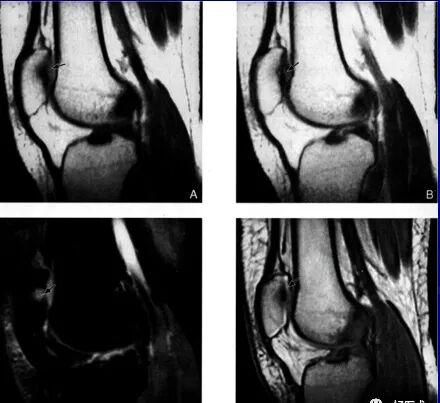

髌骨软骨软化症MRI表现:

Ⅲ级:

A:SE序列T1加权像

B:SE序列T2加权像

C:STIR像

D:PGE序列T1加权像

Ⅳ级: